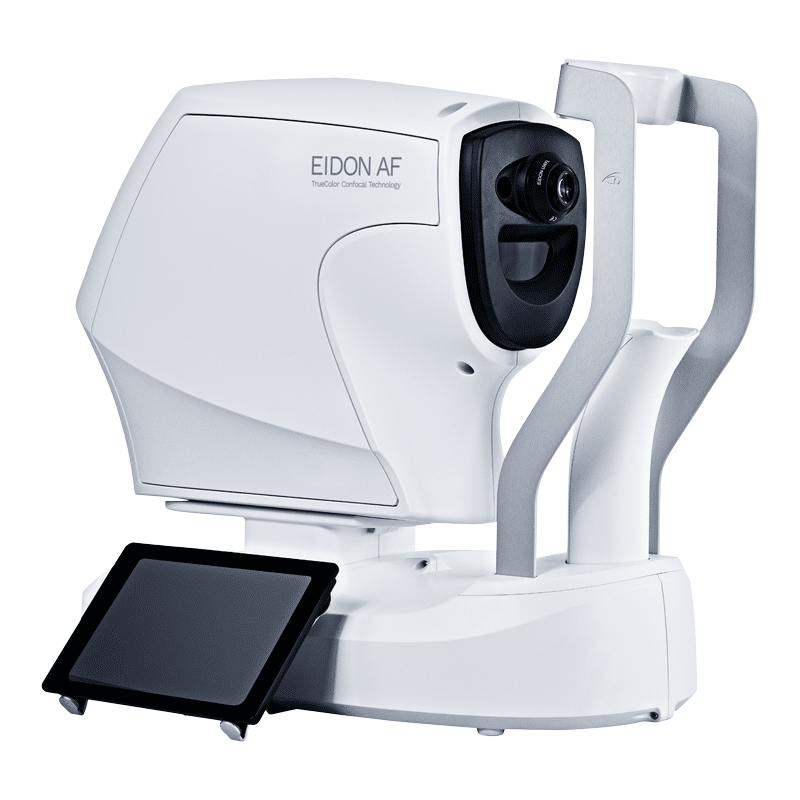

Description

EIDON AF features include:

- Crisp, sharp, and highly detailed imaging in one device

- Quick and easy-to-use – fully automated